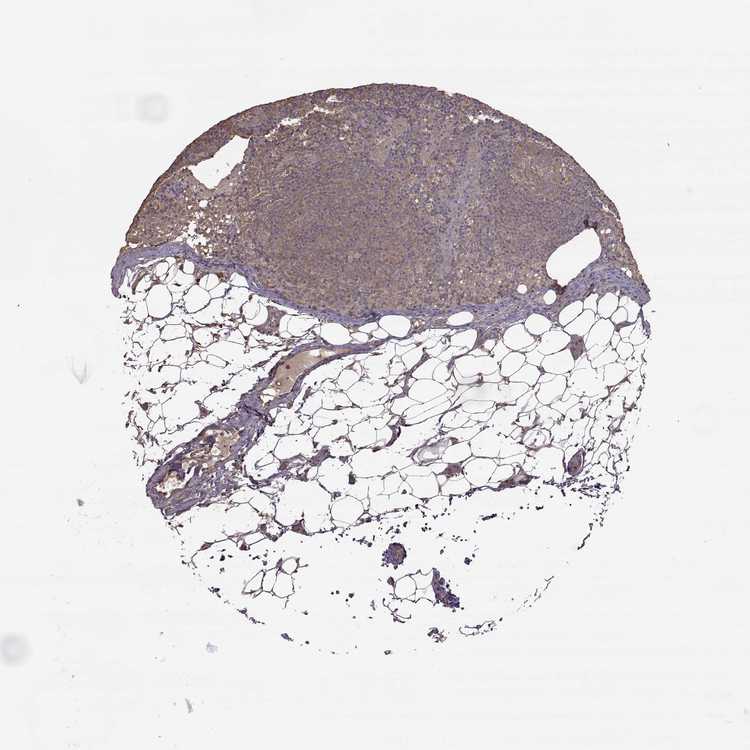

TISSUE PRIMARY DATA LYMPH NODE Show tissue menu

Lymph node

LYMPH NODE - Antibody stainingi

Antibody staining in the annotated cell types in the current human tissue is reported as not detected, low, medium, or high, based on conventional immunohistochemistry profiling in selected tissues. This score is based on the combination of the staining intensity and fraction of stained cells.

Each image is clickable and will lead to virtual microscopy that enables deeper exploration of all samples and also displays staining intensity scores, fraction scores and subcellular localization as well as patient and tissue information for each sample.

Antibody HPA008467Antibody HPA041113Antibody CAB002169Antibody CAB076057

Germinal center cells HighMediumHighMedium

Non-germinal center cells HighHighHighMedium